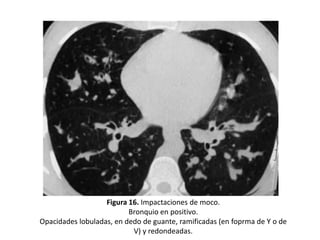

• Impactos mucoides:

– Imágenes tubulares con densidad de partes blandas que representan

el bronquio dilatado y repleto de moco: “bronquio en positivo”, o con

niveles hidroaéreos.

– Pueden aparecer como opacidades lobuladas, en dedo de guante,

ramificadas (en forma de Y o de V) o redondeadas (cuando el plano de

corte es transversal al impacto mucoso se pueden confundir con una

arteria). (Figura 16 y 17).

Figura 16. Impactaciones de moco.

Bronquio en positivo.

Opacidades lobuladas, en dedo de guante, ramificadas (en foprma de Y o de

V) y redondeadas.